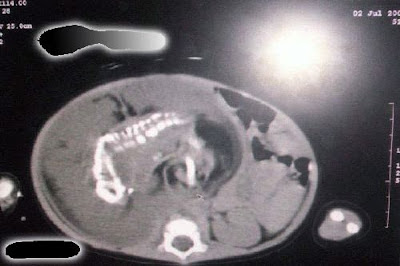

Foto-foto Bayi Mengandung Seorang Bayi

Bayi ini lahir di Arab Saudi. Bayi ini mangandung seorang bayi. Aneh bukan ? Inilah keajaiban Sang Pencipta.